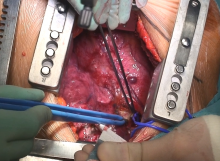

Here the authors report the case of a 50-year-old woman suffering from lymphoblastic leukemia, developing left upper lobe aspergilloma during aplastic chemotherapy, requiring orotracheal intubation for acute respiratory failure, and long-term mechanical ventilation. The patient subsequently recovered from respiratory failure and the authors were asked by their hematologists to remove the aspergilloma, a formal contraindication to therapy for hematologic disease. The patient underwent total muscle-sparing lateral left thoracotomy and extensive pneumolysis; the anomalous left upper pulmonary vein was isolated as well as the mediastinal branch of the left upper lobe artery; the vascular anatomy was slightly different from normal but without any dangerous anomalies. The left upper pulmonary vein was transected by a 30 mm gold vascular stapler and then the first mediastinal branch of the left upper lobe artery was similarly transected. Pulmonary resection was then accomplished by multiple loads of parenchymal staplers. The postoperative course was uneventful and the patient was discharged on postoperative day four.